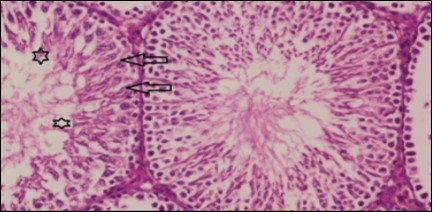

Testis Histopathological Observations

Histological examination of control rats' testis showed normal histological structure of the seminiferous tubules with an increase in the spermatogonia and other spermatocytes compared with the diabetic rats which showed an obvious decrease in the count of germinal cells generally and sloughing of germ cell in the lumen of seminiferous tubules in addition to absence of the mature sperms (Figure 3 and Figure 4). Rats tested of Fenugreek group and those treated with Glimepiride (Figure 5 and Figure 6) presented an increase in the number of spermatogenic cells and mature sperms with few focal necrotic cells. Whereas the combination therapy group showed normal histological structure of the seminiferous tubules with normal spermatogonia, presence of ledying cells and more mature of sperms (Figure 7). STZ reduced testosterone production, suggesting a decrease in the function of both Leydig (testosterone producing cell) and Sertoli (spermatogenesis) cells, which might be caused by a reduction in insulin secretion. These changes are probably due to increased Reactive Oxygen Species (ROS) production by accelerated Advanced Glycation End Products (AGE) formation 31 hexosamine and Protein Kinase C pathway. The administration of Fenugreek seeds to diabetic rats significantly decrease of sperm shape abnormality and improve the sperm count 32. Glimepiride reduced sperm abnormality and increased testis weights and sperm count by its antioxidant action 30. The potential protective efficacy of Fenugreek seed extract when added to Glimepiride was observed on reproductive systems.

Figure 7.Photomicrogragh of testis section of treated rat with combination of Fenugreek and Glimepiride showing nearly normal appearance of seminiferous tubules with organized spermatogenesis end with large number of spermatozoa (star). Note, Sertoli cells (arrows). (H&E) (40X).

Photomicrogragh of testis section of treated rat with combination of Fenugreek and Glimepiride showing nearly normal appearance of seminiferous tubules with organized spermatogenesis end with large number of spermatozoa (star). Note, Sertoli cells (arrows). (H&E) (40X).